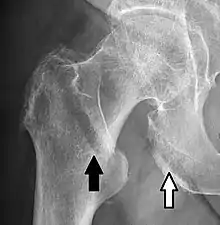

Imaging

Typically, radiographs are taken of the hip from the front (AP view), and side (lateral view). Frog leg views are to be avoided, as they may cause severe pain and further displace the fracture.[5] In situations where a hip fracture is suspected but not obvious on x-ray, an MRI is the next test of choice. If an MRI is not available or the patient can not be placed into the scanner a CT may be used as a substitute. MRI sensitivity for radiographically occult fracture is greater than CT. Bone scan is another useful alternative however substantial drawbacks include decreased sensitivity, early false negative results and decreased conspicuity of findings due to age-related metabolic changes in the elderly.[16]

X-rays of the affected hip usually make the diagnosis obvious; AP (anteroposterior) and lateral views should be obtained.